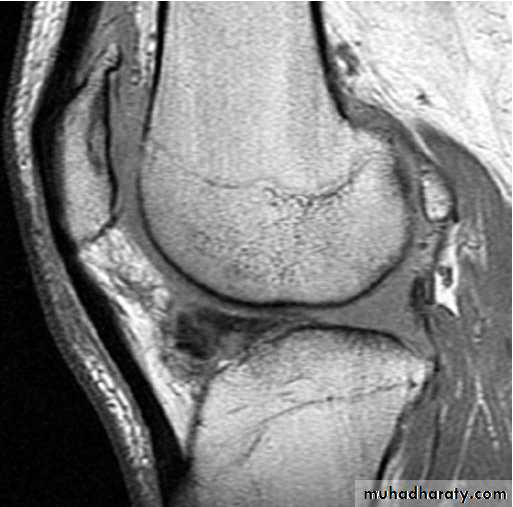

MRI

Axial loading + flexion + rotationTypes of meniscal tear

Vertical longitudinalBucket – handle

TransverseOblique

Horizontal cleavage : degenerativeC / F

PainGiving way

LockingSwelling : 24 hrs after trauma

O / ETenderness

Fluid inside the joint

Mc Murray testDx

XR : normal

Arthroscopy